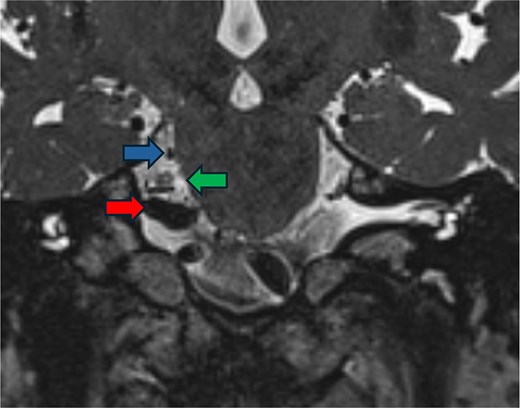

A 78-year-old male presented with 3 weeks of severe lancinating pain radiating into the right side of his face and jaw. The pain distribution matched the innervation pattern of the third branch of the trigeminal nerve. These episodes occurred 25–30 times per day, were short-lived, and were rated as severely painful with associated paresthesias. He was started on carbamazepine based on clinical suspicion for trigeminal neuralgia. A noncontrast MRI of the brain with fast imaging employing steady-state acquisition (FIESTA) sequence [9] showed a dolichoectatic, high-riding, and eccentric right vertebral artery compressing the inferior trigeminal nerve (Fig. 1). The decision was made to take the patient for MVD of the trigeminal nerve.

Preoperative imaging. FIESTA scan demonstrating the compression of the trigeminal nerve (green arrow) by the vertebral artery (red arrow) inferiorly and the superior cerebellar artery (blue arrow) superiorly.